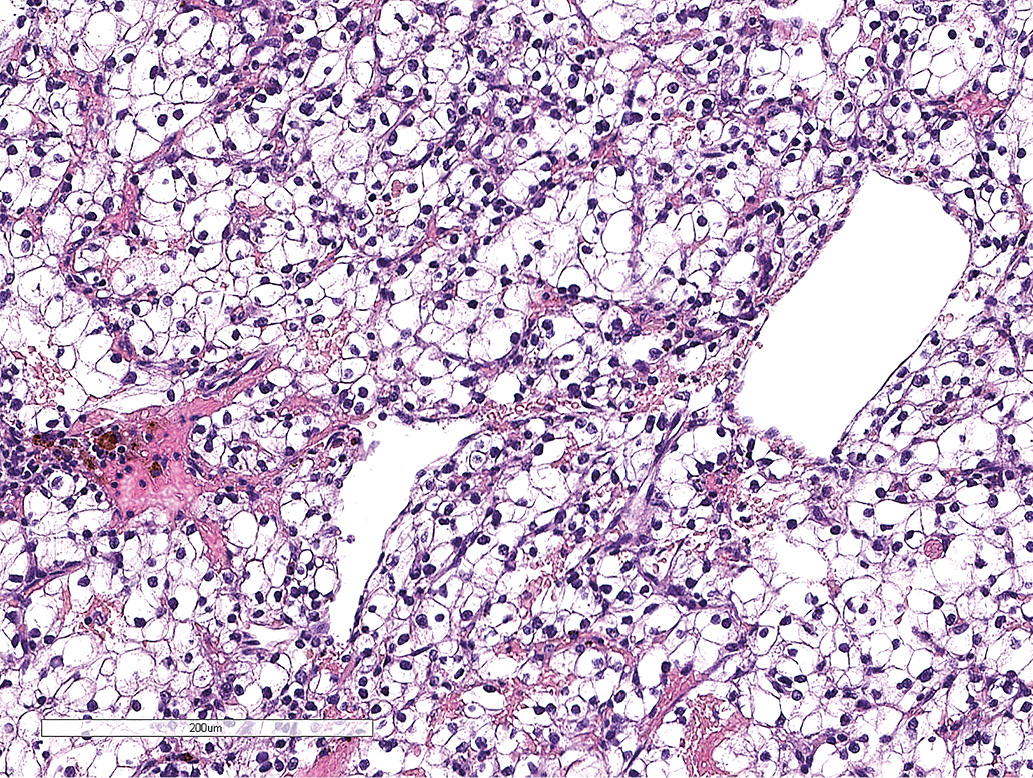

Пациенту выполнено трансназальное трансфеноидальное удаление опухоли в марте 2023 г. Операционный материал был представлен фрагментами ткани опухоли из клеток с оптически светлой цитоплазмой, расположенные в тонкой сосудистой сети (рис. 3.2), позитивные к CD10 при иммуногистохимическом исследовании (рис. 3.3). Ткань нейро- и аденогипофиза не получена. Диагностирован метастаз светлоклеточного почечноклеточного рака.

Рисунок 3.2. Окраска гематоксилином и эозином. Метастаз светлоклеточного почечноклеточного рака.

Рисунок 3.3. Иммуногистохимическое исследование: окрашивание клеток опухоли с антителами к CD10.